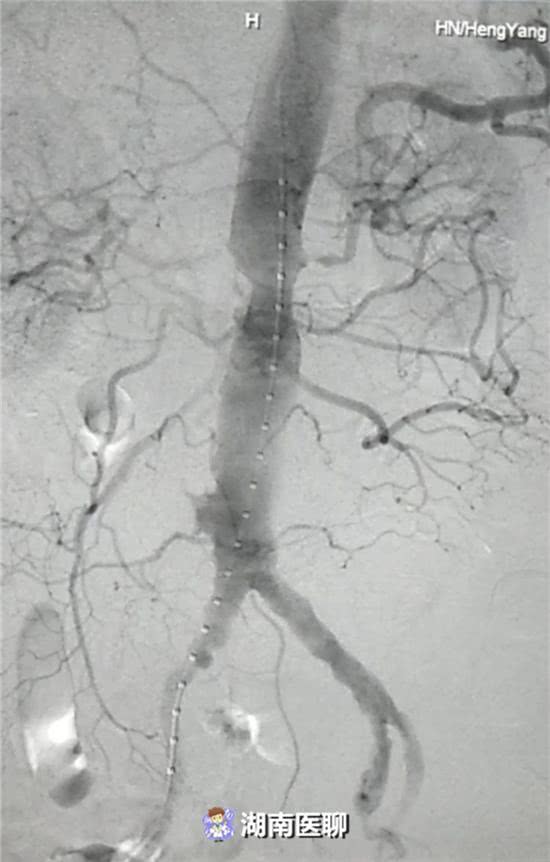

血管介入科排除各種困難,在麻醉科協(xié)作下行腹主動(dòng)脈瘤覆膜支架隔絕術(shù)(“褲衩”支架植入)。

(血管介入科行腹主動(dòng)脈瘤覆膜支架隔絕術(shù))